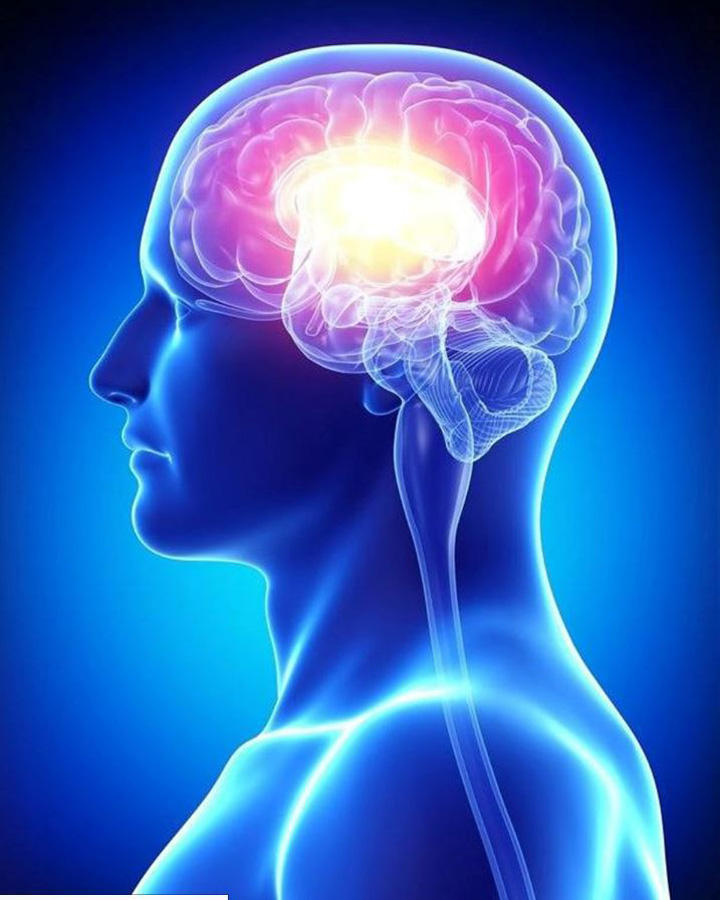

1.Те, которые связаны с поражением головного мозга, например черепно-мозговая травма, его онкологические заболевания и инсульт;